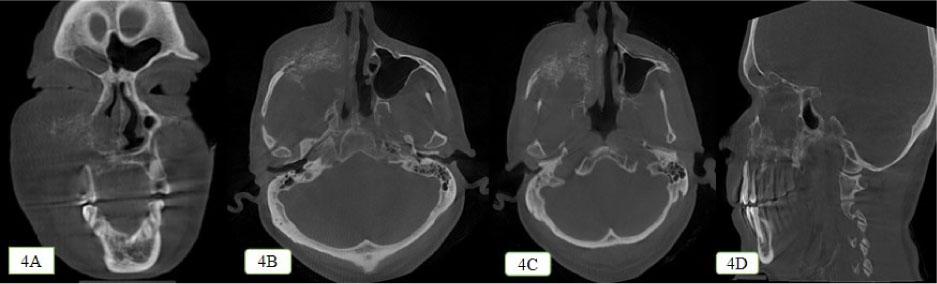

The destruction pattern manifested in the form of radiolucent spikes like projections seen arising within the anterolateral wall of right maxillary sinus mimicking the sun ray appearance as seen in osteosarcoma (Figure 4A–4D).

The unique radiographic pattern shown by adenocarcinoma as a result of destruction. 4A: Coronal section showing the mixed radiolucent radiopaque lesion causing destruction of nasal septum and giving rise to sunburst appearance. 4B and 4C: Axial section showing the mixed radiolucent radiopaque lesion showing destruction of nasal septum and zygoma giving the sunburst appearance. 4D: Sagittal section showing the sunburst pattern with respect to the floor of right maxillary sinus and nasal septum along with bone loss seen with respect to 13–18 region.

The lesion was seen crossing the midline in the posterior region with complete destruction of floor of orbit and cortical bone on the right side (Figure 5A–5D). Haziness was seen within the substance of sphenoidal sinus, right maxillary, ethmoidal, and frontal sinuses, indicating the involvement of paranasal sinuses.

Destruction pattern of the lesion in axial view. 5A: Destruction of the right lateral wall of nasal cavity and inferior turbinates. 5B: Mixed radiolucent radiopaque lesion caused destruction of anterolateral and posterolateral wall and floor of right maxillary sinus and nasal cavity. 5C: The mixed radiolucent radiopaque lesion seen crossing the midline of the palate at the posterior region. 5D: Mixed radiolucent radiopaque lesion produces sunburst appearance at the right zygoma region

Because of the mucin content inside, sinonasal adenocarcinomas usually show up as soft-tissue masses with calcified patches. For higher grade lesions in particular, they can lead to bone degradation. In our case, the lesion exhibited a sunray appearance constituted by thin, straight bony spicules that resulted from a periosteal bone response. Osteosarcoma, chondrosarcoma, Ewing sarcoma, central hemangioma, and metastatic prostate and breast malignancies are among the highly aggressive and rapidly developing tumors that most frequently exhibit this hypothesized pattern and should be considered in the radiographic differential diagnosis[16].

In contrast to adenocarcinomas, which might show expansion or destruction, osteosarcomas demonstrate aggressive bone destruction. Although both may manifest as a soft-tissue tumor, calcifications indicative of mucin synthesis are more common in adenocarcinomas. The “sunburst” periosteal reaction is characteristic of osteosarcomas, but adenocarcinomas could exhibit less noticeable periosteal alterations. Radiographically, the new bone matrix produced by osteosarcomas can be visualized, whereas in case of adenocarcinoma, this feature is absent[17].